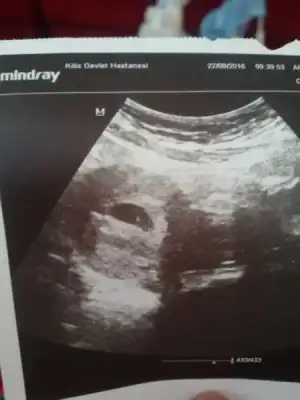

Havalianne__ Havalianne__ burda benim bebeğim 8+5 haftalık. Kese yuvarlaksa kız fasulye gibiyse erkek miydi. Benimki tam yuvarlak da değil tam fasulyede değil sanki. Ona göre bi bakar mısın

• IMG_20160825_091750.webp

IMG_20160825_091750.webp

15 KB · Görüntüleme: 85